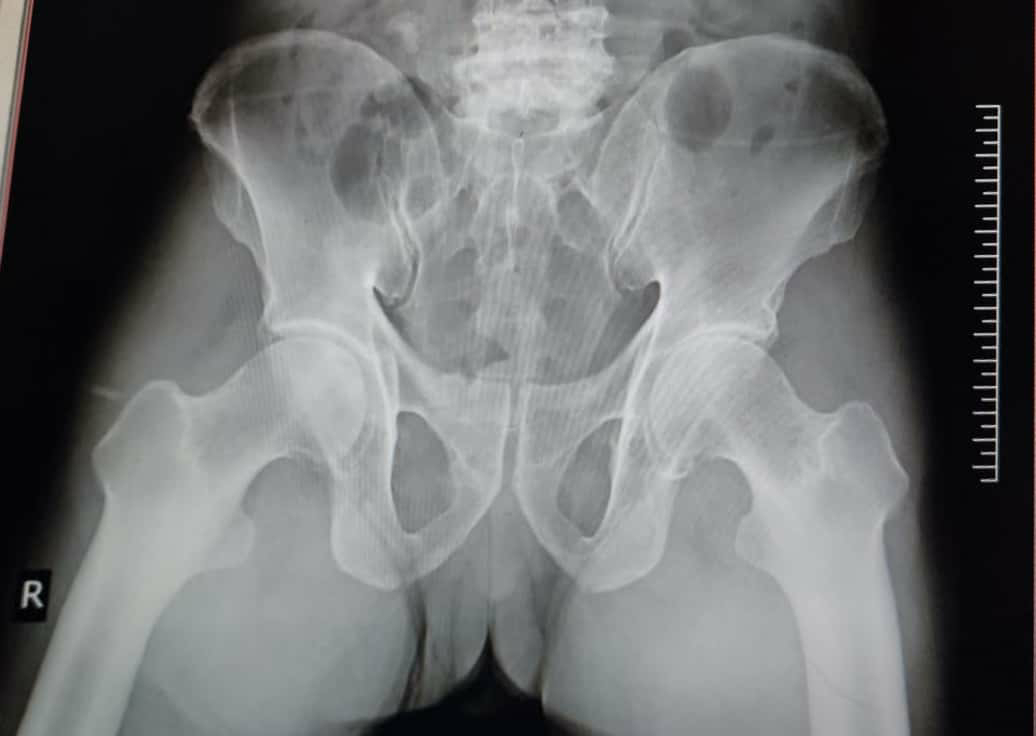

CBPINVESTIGATIONS DONE ON 21/7/21Pelvis-AP viewINVESTIGATIONS DONE ON 22/7/21Hemogram Blood urea level is so much high which should have been maintained by normal kidneys.Hb level was decreased may be due to loss of Hb through kidneys.The main thing is there is decreased creatinine clearence.CREATININECreatinine is an endogenous athreshold substance for kidney which should be excreated in urine.creatinine is formed by LOHMANN REACTION.The creatine formed here undergo some spontaneous reactions which leads to formation of CREATININE.EXCREATION OF CREATININE.Creatinine is cleared from plasma by GFR.and there is also some secreation by tubules into the lumen and creatini ne excreation takes place.so if there is problem with creatinine clearence then we can expect renal failure.Treatement and prophylactic treatemebt was given and it is nice.she had presented a case on CKD.it was good but there are no perfect reports posted in log book.but the treatement was good based on investigation done.LFT says that bilirubin levels are increased , enzyme panel is also disturbed RFT says that UREA,URIC ACID and CREATININE LEVELS are abnormal indicating renal failure.treatement is good and satisifactory.Now at present the patient have shifted to ORTHOPAEDIC DEPARTMENT.She had presented a case on diabetes with breathlessness.the patient was also suffering from fever and diarrhoea.the patient is diabetic since 4 years.General examination and systemic examination was found to be normal.VITALSfluctuation of BP.temperature was afebrile.INVESTIGATIONS DONE AREAbdominal examination :- Soft